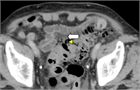

1. 大腸憩室炎と大腸憩室出血の典型例

大腸憩室炎

1. 大腸憩室炎は急性期に、膿瘍形成、腸閉塞、瘻孔形成、穿孔、腹膜炎などの状態を合併することがある。